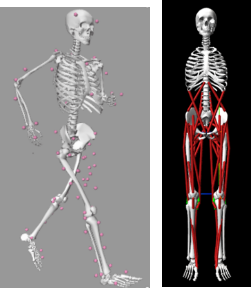

(2) Computational Biomechanics 计算生物力学

Inverse/Forward dynamics 逆向动力学/正向动力学

图注:FEM 有限元分析、力动学分析、骨与关节数字建模

图注:逆动力学分析